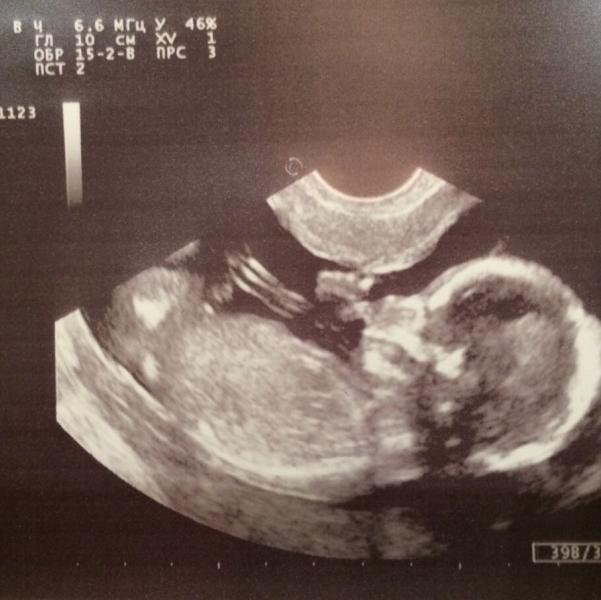

1 октября сходили на УЗИ и увидели нашу радость 🤗 Врач сказал, что все хорошо, ттт, все нравится, малыш развивается хорошо. Естественно хотели посмотреть пол ребёнка и тут понеслась 🙈 ноги скрестил, пяткой писю закрыл и все попытки рассмотреть были тщетны. Естественно папа подметил, что вся вредность - это в маму🌚 В итоге решили мы не сдаваться и поехать 2-го октября к другому гинекологу на УЗИ , врачу тоже все понравилось, с малышом все прекрасно. И тут папа занервничал, когда на экране не было...